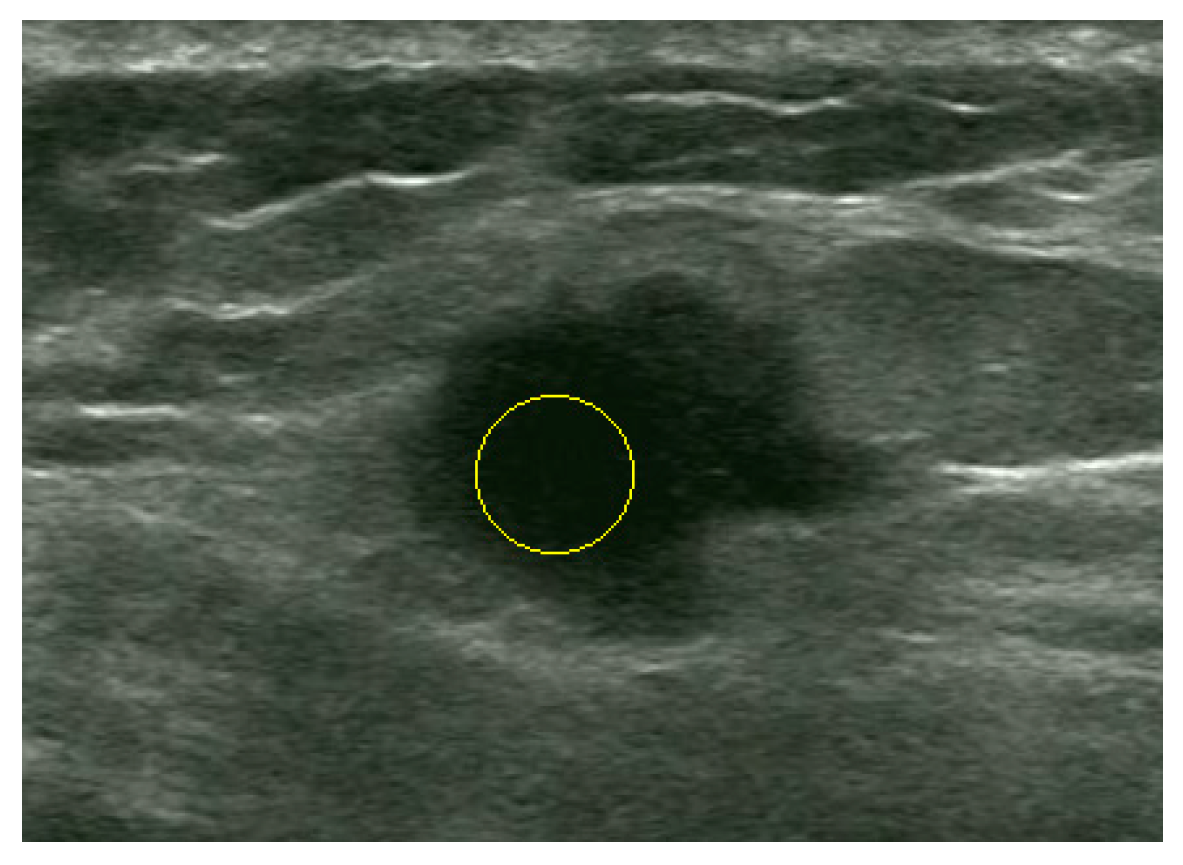

An Automatic Localization Algorithm for Ultrasound Breast Tumors Based on Human Visual Mechanism

Xie, Y.; Chen, K.; Lin, J. An Automatic Localization Algorithm for Ultrasound Breast Tumors Based on Human Visual Mechanism. Sensors 2017, 17, 1101. https://doi.org/10.3390/s17051101